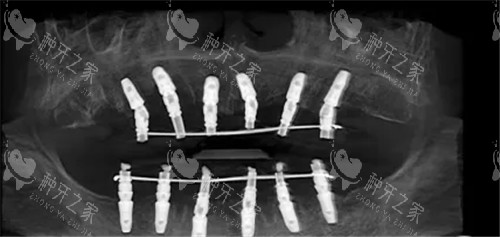

全口种植ct图片